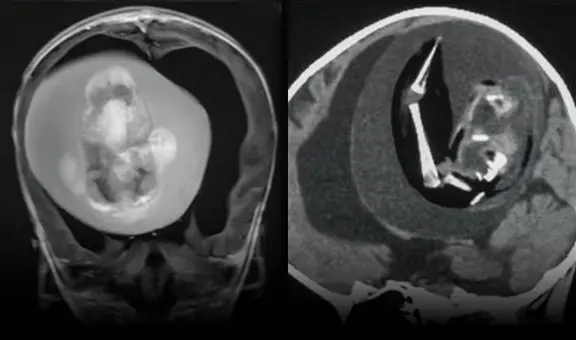

Las autoridades recurrieron entonces al drenaje de los pozos sépticos de las viviendas, en los que encontraron restos de tejido humano, tras lo cual Xu fue arrestado y confesó a las autoridades que la asesinó en la mañana del 5 de julio del 2020 tras echar somníferos en su bebida.